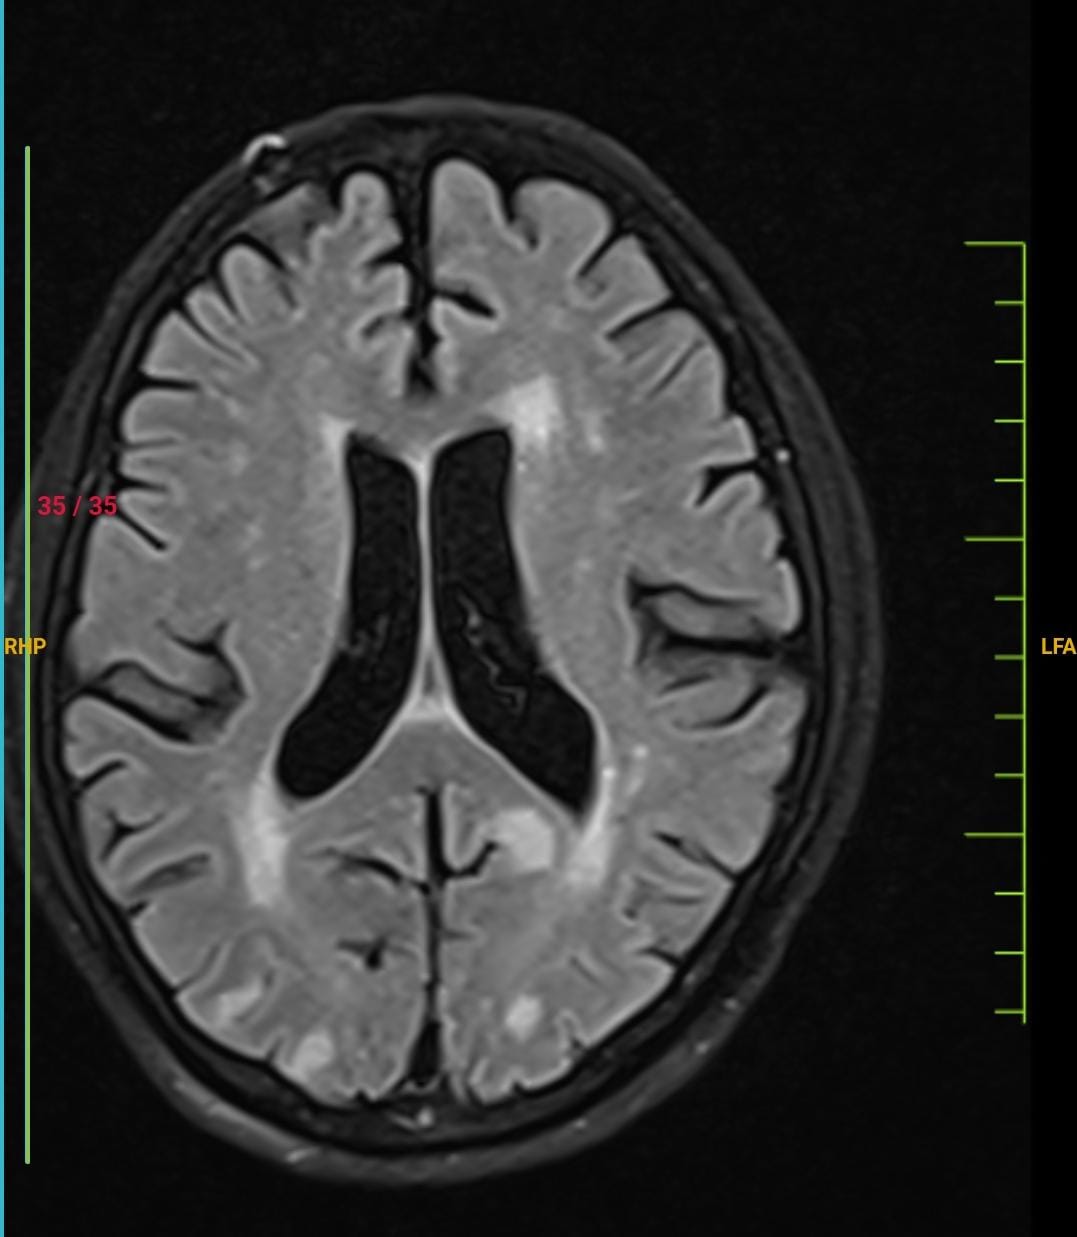

60M with metabolic syn phenotype, diabetes, hypertension 3 years and bilateral chronic knee osteoarthritis with recent PUO and cough since 1 month presented with sudden left upper limb monoparesis and shortness of breath. The serial chest X-rays were suggestive of cardiogenic pulmonary edema which was morphologically consistent with HFPeF on echocardiography showing LVH and LA dilation but a closer look at his HRCT revealed chronic cavitary lesions suggestive of tuberculosis and even as we spoke the CBNAAT for TB came positive and the MRI showed vasculopathy that could explain his sudden monoparesis. The confluence of CD and NCD has been a recurrent clinical complexity theme of late and in this instance the complexity was compounded by the fact that the stroke may have been either due to the CD or NCD driven vasculopathy although anatomical arterial territory of involvement may provide clues to differentiate further.

:98% @ RA. O/E HYPOTONIA PRESENT IN LEFT UPPERLIMB WITH POWER 4/5 IN LEFT UPPER LIMB AND LOWER LIMB, EXTENSOR PLANTAR ON LEFT SIDE . ON AUSCULTATION Crept Present IN B/L IAA,ISA,MA. MRI BRAIN SHOWED MULTIPLE TINY TO SMALL INFARCTS Involving CORTEX AND SUBCORTICAL WHITE MATTER OF B/L PARIETAL LOBES, HRCT CHEST SHOWED MODERATE CYSTIC BRONCHIECTASIS WITH INTERVENING LUNG PARENCHYMAL FIBROSIS SEEN IN THE RIGHT Upper Lobe ANTERIOR SEGMENT AND RIGHT MIDDLE LOBE.SMALL THICK WALLED CAVITORY LESION IN RIGHT LOWER LOBE LATERAL BASAL SEGMENT.MULTIPLE OTHER PATCHY AREAS OF CONSOLIDATION IN BILATERAL LUNGS.MULTIPLE SUBCENTRIMETRIC MEDIASTINAL LYMPH NODES. SPUTUM FOR TRUNAAT SHOWED MTB, RIFAMPICIN SENSITIVE AND SMEAR SHOWED AFB BACILLI. DIAGNOSED AS TUBERCULAR VASCULITIS WITH ACUTE CVA LT HEMIPARESIS, SEPSIS SECONDARY TO TUBERCULAR BRONCHIECTASIS, AKI ON CKD , MODERATE NON PROLIFERATIVE DIABETIC RETINOPATHY, K/C/O DM II , HTN SINCE 3 YEARS.TREATED WITH IONOTROPES I/V/O SEPTIC SHOCK , IV FLUIDS, ANTIBIOTICS, ANTIPYRETICS, STEROIDS. STARTED ON ATT ON 4/10/24 WITH HRZE REGIMEN AND OTHER SUPPORTIVE TREATMENT. PATIENT WAS IMPROVED CLINICALLY AND DISCHARGED IN HEMODYNAMICALLY STABLE CONDITION.

MRI BRAIN PLAIN (1/10/24): MULTIPLE TINY TO SMALL ACUTE INFARCTS INVOLVING THE CORTEX AND SUBCORTICAL WHITE MATTER OF BILATERAL PARIETAL LOBES.FEW TINY FOCI OF ACUTE INFARCTS Involving BILATERAL FRONTAL LOBES . FAZEKA'S GRADE II CHRONIC SMALL VESSELS WHITE MATTER ISCHEMIA.